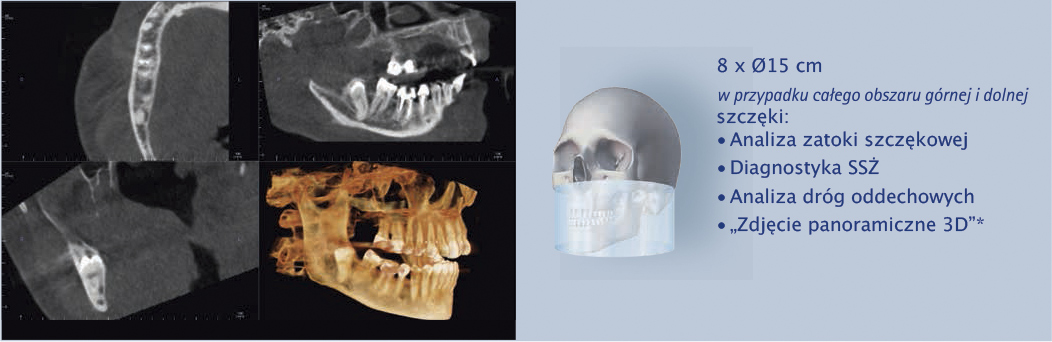

Cztery różne pola obrazowania zapewniają niezawodną diagnostykę 3D w całym obszarze jamy ustnej. Zapewniają one precyzyjne dopasowanie, odpowiednie do wskazań a także uniwersalne możliwości zastosowania w codziennej praktyce – od endodoncji, poprzez implantologię do chirurgii jamy ustnej.